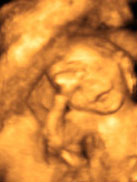

Малыш может спокойно, как ему захочется перемещаться внутри матки, при этом получая массу удовольствия. Ваш ребенок очень активен, особенно Вы можете почувствовать это по ночам, когда Вы отдыхаете. Если кувырки, толчки крохи и прочие проявления активности сильно беспокоят Вас, погладьте свой животик, поговорите с малышом, напойте ему песенку.

Ваш малыш способен на многое: сжимает и разжимает пальцы рук, играет пуповиной, закрывает ручками лицо, кувыркается, сосет пальчик.

Продолжает формироваться родовая смазка на теле малыша, она защитит нежную кожу крохи от околоплодных вод. Эта смазка сохраняется до самого рождения малыша.